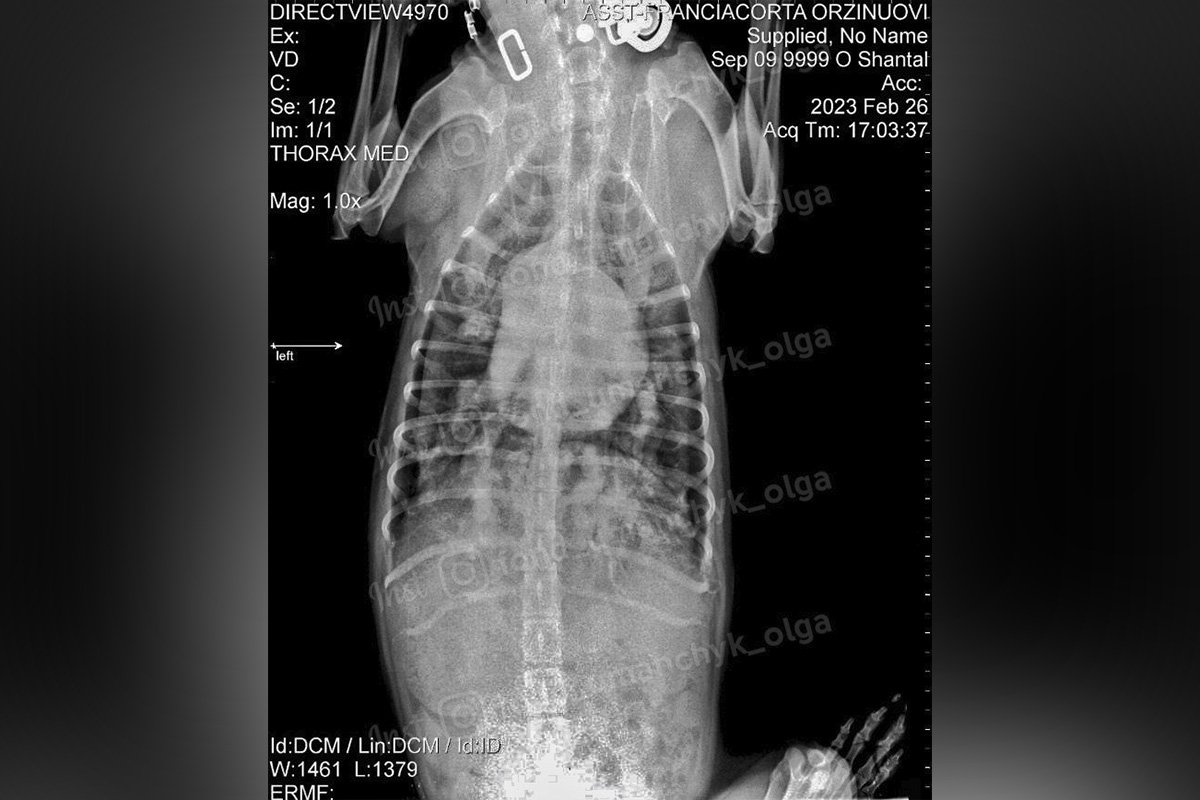

Шанталь опинилась на вулиці, її викинули на дачі. Вона ледь-ледь тримається на ногах. У нещасної сім літрів рідини в черевній порожнині. Асцит. Голова фонду "Ми за право на життя" Ольга Уманчик не виключає онкозахворювання, та на Шанталь ще чекає консультація онколога. На жаль, це не єдина проблема фонда, який опікується собачкою. В них є котики-"британці", яким терміново треба знайти нових власників.

За словами волонтерки, велика кількість рідини в черевній порожнині у Шанталь є симптомом. Втім, це вказує на серйозне захворювання, яке потребує негайної діагностики та лікування. Є ймовірність, що це онкологія, але перш за все, собачку слід показати онкологу. Наразі Шанталь капають, вона отримує першу допомогу, але краще від цього не стає.

"Якщо знайдуть онкозахворювання, не уникнути 10 блоків хімії. На все потрібно не менш 10 тисяч грн", - пише Ольга Уманчик і додає, що фонд має борг - 2 тисячі грн.